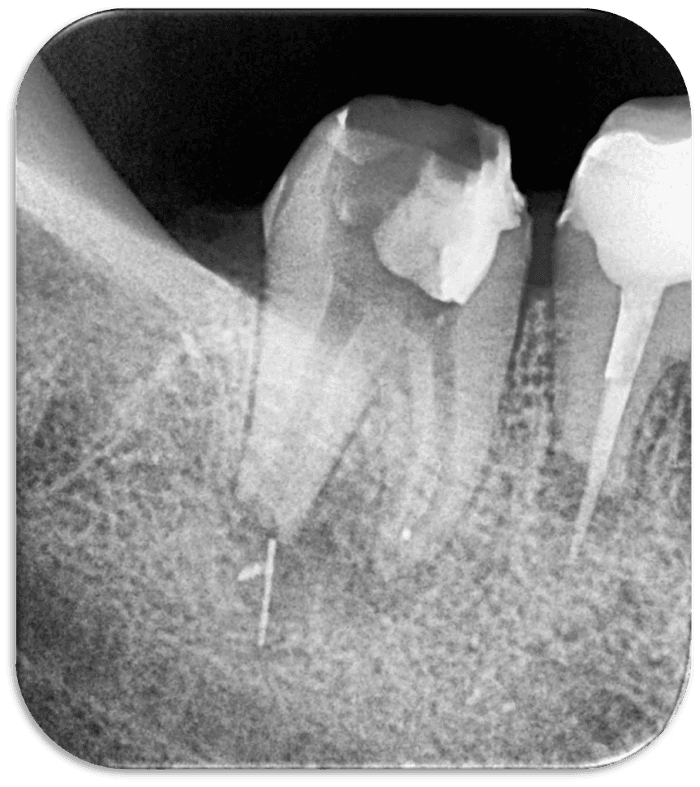

Rubberdam izolasyonu sonrası tedaviye başlandı. Geçici dolgu kaldırıldığında distal kanalın apikalinde guta ve eğenin koronal bölümü izlendi (RESİM 2).

RESİM 2: Başlangıç fotoğrafı apikalde eğe ve guta